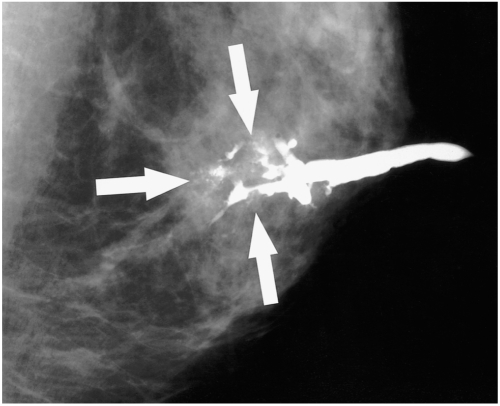

Complete Ductal Obstruction

Complete ductal obstruction is not pathognomonic of breast cancer, and can be observed in both benign and malignant tumors. This finding was noted in 5-47% of benign diseases, and in 67-83% of cancers, by ductography (7, 8). In approximately 70% of obstructing papillomas, contrast material was observed to partially outline the leading edge of a lesion, resulting in a meniscus-like appearance (7, 8). By way of contrast, the shape of the cut-off site in the carcinoma on ductography often assumes an irregular, moth-eaten appearance (Fig. 1). According to these reports, this moth-eaten appearance was observed in 56-76% of cancers (8, 9). In addition, an irregular-shaped mass is often observed at the point of malignant obstruction.

Fig. 1.

A 52-year-old woman with a 2.2 cm ductal carcinoma in situ with microinvasion who presented with bloody nipple discharge. The mediolateral oblique ductogram reveals complete obstruction with a distal, irregular, moth-eaten appearance (arrows), and associated microcalcifications.